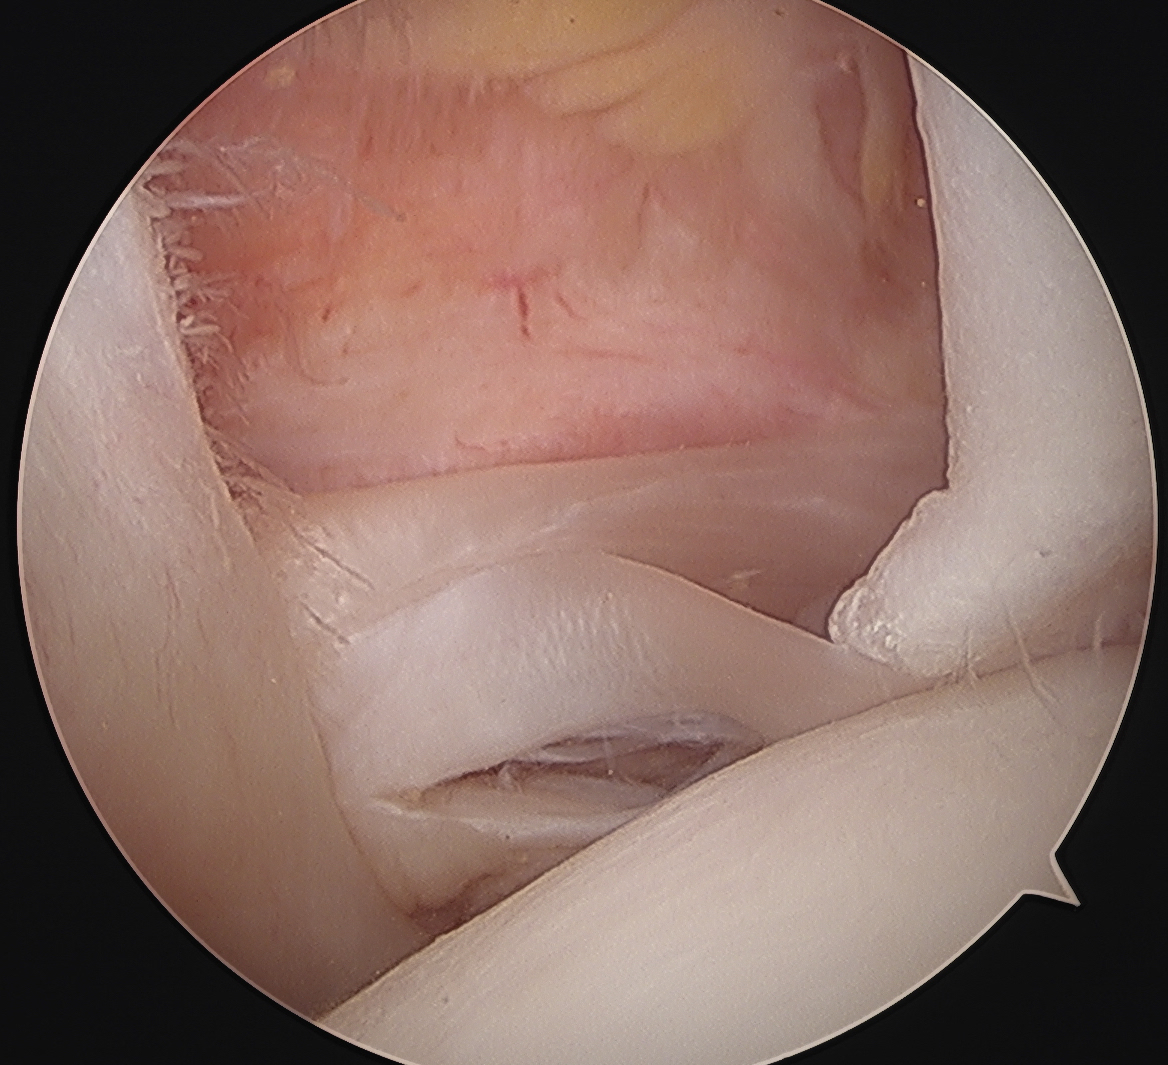

Arthroscopy

Medial subluxation of LBH with subscapularis tear

Options

Subscapularis repair + Tenodesis / Tenotomy

Subscapularis repair with LHB stabilization

Subscapularis repair + biceps tenodesis